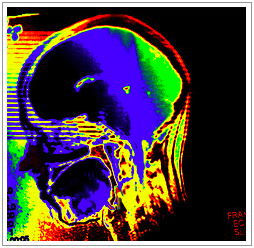

Vrais et faux souvenirs emprunteraient des voies nerveuses différentes dans le cerveau.

L’étude de la substance blanche [1] permettrait de mieux connaître les régions cérébrales concernées par la remémoration des vrais et faux souvenirs. C’est ce que révèle le travail d’une équipe de recherche dirigée par Lluís Fuentemilla, de l’Université de Barcelone en Espagne.

Que nous disent les données de neuroimagerie recueillies par les chercheurs pendant la réalisation de ce test ? Elles indiquent que le faisceau longitudinal inférieur, ensemble de fibres nerveuses connectant différentes structures du lobe temporal médian (dont l’hippocampe [2]), est impliqué dans la remémoration de vrais souvenirs (mots étudiés), alors que le faisceau longitudinal supérieur, connectant les régions frontales et pariétales du cerveau, est impliqué dans la récupération de faux souvenirs (mots critiques).

Vrais et faux souvenirs emprunteraient donc des voies nerveuses différentes, dévoilant ainsi les zones cérébrales concernées par la remémoration des expériences vécues et celles jouant un rôle dans les illusions mnésiques.